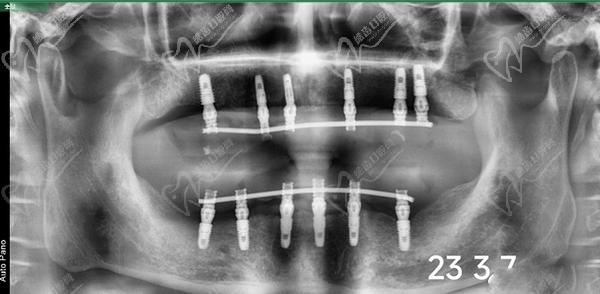

全口即拔即種即刻負(fù)重種植牙一般分為兩期,一期手術(shù)是在拔除牙齒后立即植入種植體,戴臨時(shí)牙冠,等待創(chuàng)口愈合;二期手術(shù)則是待創(chuàng)口愈合后,進(jìn)行固定牙冠佩戴。全口即拔即種即刻負(fù)重可以同時(shí)全口做,也可以先上頜后下頜。在每期手術(shù)之間,醫(yī)生會根據(jù)患者的具體情況進(jìn)行相應(yīng)的藥物治療和護(hù)理指導(dǎo)。

牙友1、前天結(jié)束的全口種植牙,拔牙加同期種12顆瑞士士卓曼,即刻負(fù)重!全口牙周炎伴隨多顆牙松動且骨量不足等問題,普通的種植手術(shù)無法滿足生活需求,想要做即拔即種即刻戴上臨時(shí)牙,因?yàn)槌R?guī)的植骨手術(shù)需要等待很長時(shí)間。經(jīng)過正規(guī)醫(yī)院骨質(zhì)評估分析,上頜AO4+兩邊穿翼手術(shù),患者手術(shù)結(jié)束當(dāng)天就可以正常用牙,本人表示非常高興和滿意!感謝醫(yī)院團(tuán)隊(duì)協(xié)作!